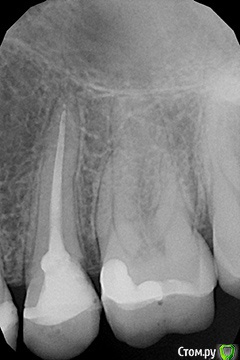

Bier Опубликовано 12 марта, 2017 Поделиться Опубликовано 12 марта, 2017 на мой взгляд на зубе есть периодонтит. Либо полечить снова с микроскопом, либо резекцию сделать. Пазуха выглядит лучше. У каких ЛОРов вы наблюдаетесь? Ссылка на комментарий

Verasss Опубликовано 13 марта, 2017 Автор Поделиться Опубликовано 13 марта, 2017 Благодарю врачей за ответы! Гайморита нет и не было. Были лицевые боли. И сейчас бывает при перепаде температур окр. среды (не еды), в щеке и наверху челюсти. Жалоб конкретно на зуб у меня нет, меня он волнует только с точки зрения вреда, какой он может нанести в дальнейшем пазухе. Как проверяют на трещину корня? Если я правильно понимаю, если она б у меня была, я не могла бы им есть и он бы болел? Ем я им нормально. Вот снимок сегодня. Спасибо! Ссылка на комментарий